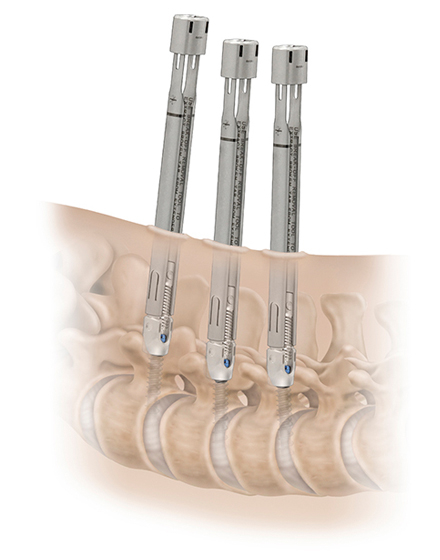

最小侵襲脊椎安定術 MISt(ミスト)

適応となる疾患:転移性脊椎腫瘍、化膿性脊椎炎、脊椎骨折など

がんの脊椎転移、脊椎の細菌感染、外傷による脊椎骨折など脊椎の安定性が失われた病態に対して行われる低侵襲な手術です。脊椎に挿入する金属スクリューを、経皮的に刺入するために皮膚切開が小さく、筋肉に対するダメージを最小限にすることができます。出血量も低減させ、早期離床、早期リハビリが可能な手術です。術後の安静期間や入院期間は病態に応じて異なります。

出典元:HIkata et al. Clinical Spine Surgery 2016 in press